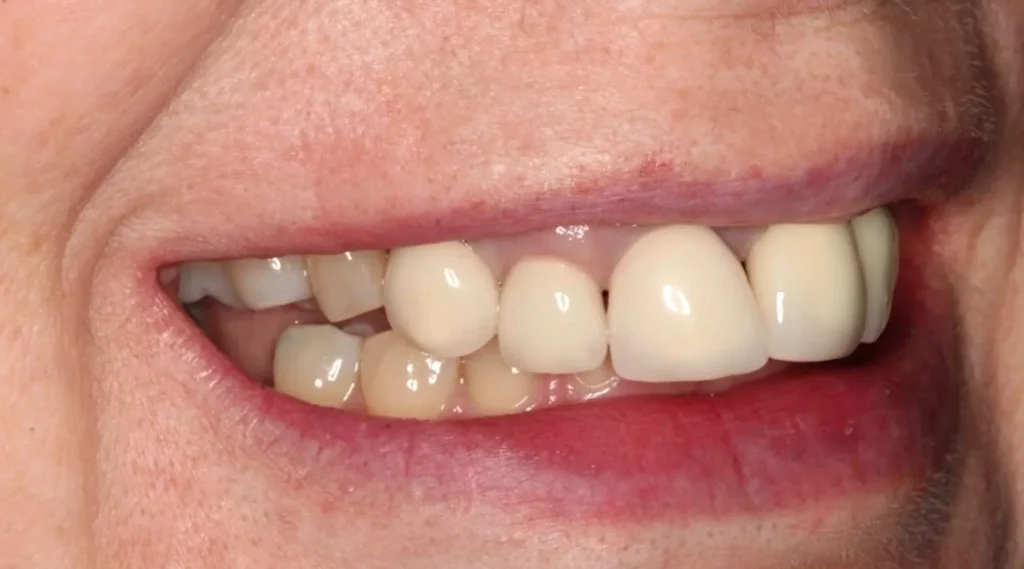

This lady attended Gentle after a previous implant had not worked. In the left photo below is a temporary bridge that kept falling out, which was frustrating for the patient, so she wanted to try again with implant treatment. Moreover, when she smiled, the adjacent eye tooth had an exposed root, so it looked too long. At the same time as placing gum around the implant, a gum graft was placed to cover the exposed eye tooth root. This improves the overall aesthetic outcome for the patient. Below on the right you can see how we took time to rebuild the bone and gum in the first phase of treatment, which gave the implant a solid foundation to sit in.

The implant was placed into the bone, under the gum, and a white post was chosen to fit into the implant to maximise the final crown’s appearance. The after photo was taken 5 years after the implant was placed and shows how nicely the work is performing.